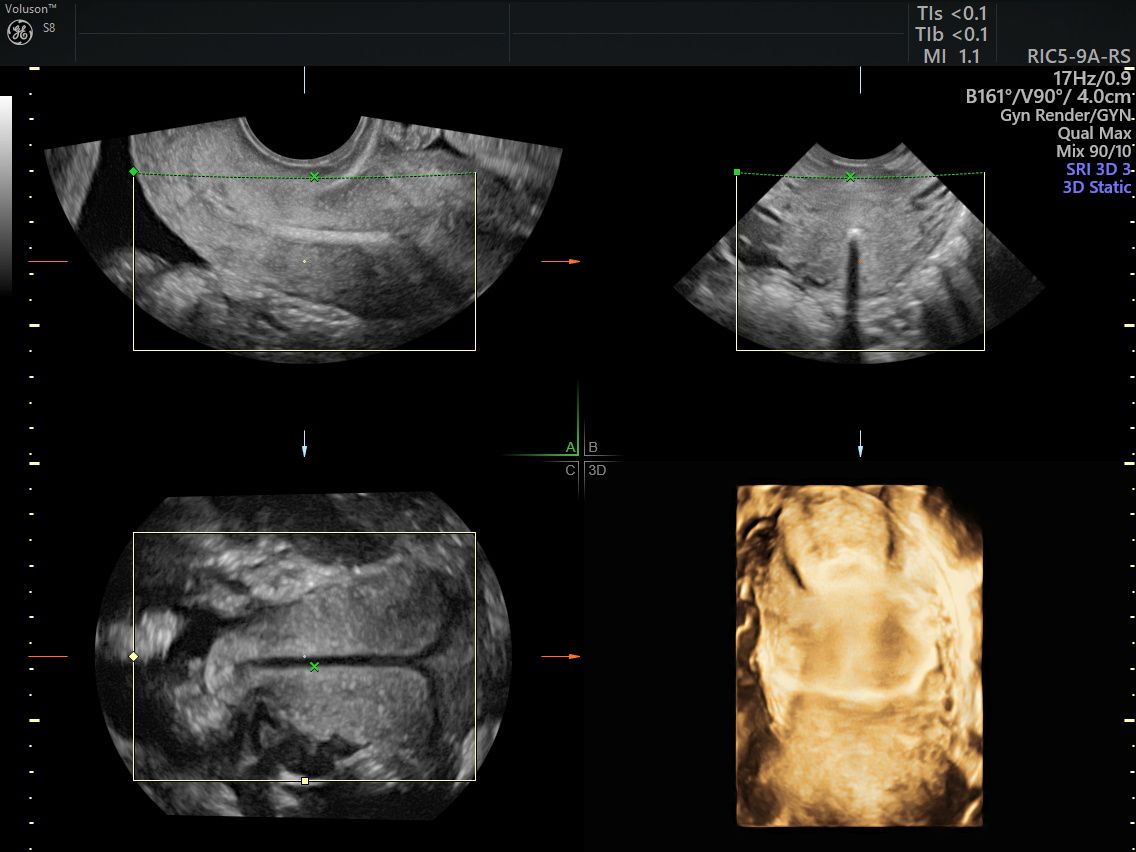

Eseguo in particolare ecografie ostetriche e ginecologiche anche in 3D e 4D per meglio identificare la problematica, offrire diagnosi precise ed un trattamento mirato e personalizzato.